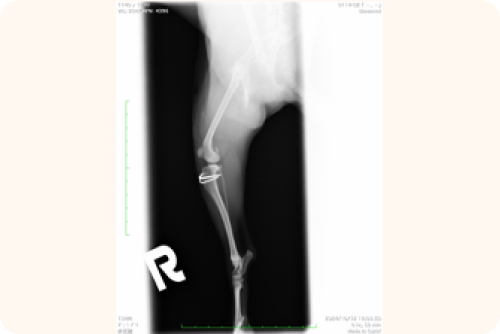

レントゲン検査

X線撮影により、以下の点を詳細に確認します。

• 膝蓋骨の位置と脱臼の方向

• 骨の変形や捻れ

• 変形性関節症の進行度

• 関節炎の有無

この検査結果は、手術の必要性や具体的な手術方法を決定する上で重要な情報となります。